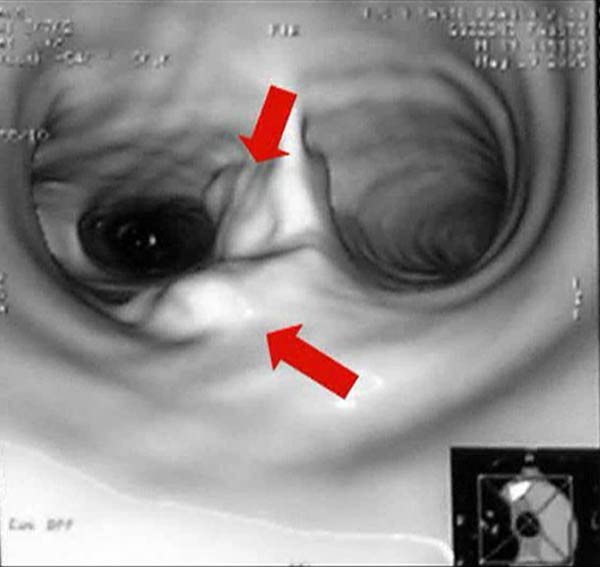

Cardiac function is assessed based on a physical examination, electrocardiography, and transthoracic echocardiography in all patients. Radiological work-up includes standard chest X-ray, total body CT-scan, bone scintigraphy and PET scan, where indicated. All patients should be submitted to rigid bronchoscopy (Figure 3) and sometimes to virtual bronchoscopy (Figure 4) to precisely assess the extent of invasion and the required resection. Mediastinoscopy (in case of malignant tumors), performed at the time of planned resection, may be useful to discover potentially involved lymph nodes, to evaluate the mediastinal and extraluminal spread of the neoplasm and to dissect the pretracheal plane, enhancing the mobility of upper trachea and reducing the risk of recurrent laryngeal nerve injury.